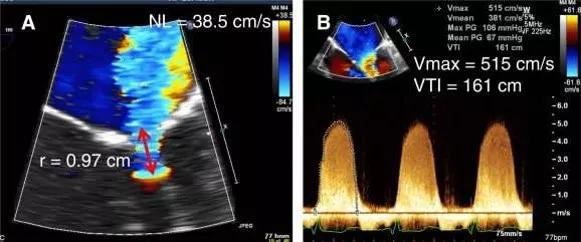

超声心动图十大基本功8.2:二尖瓣关闭不全的超声评估